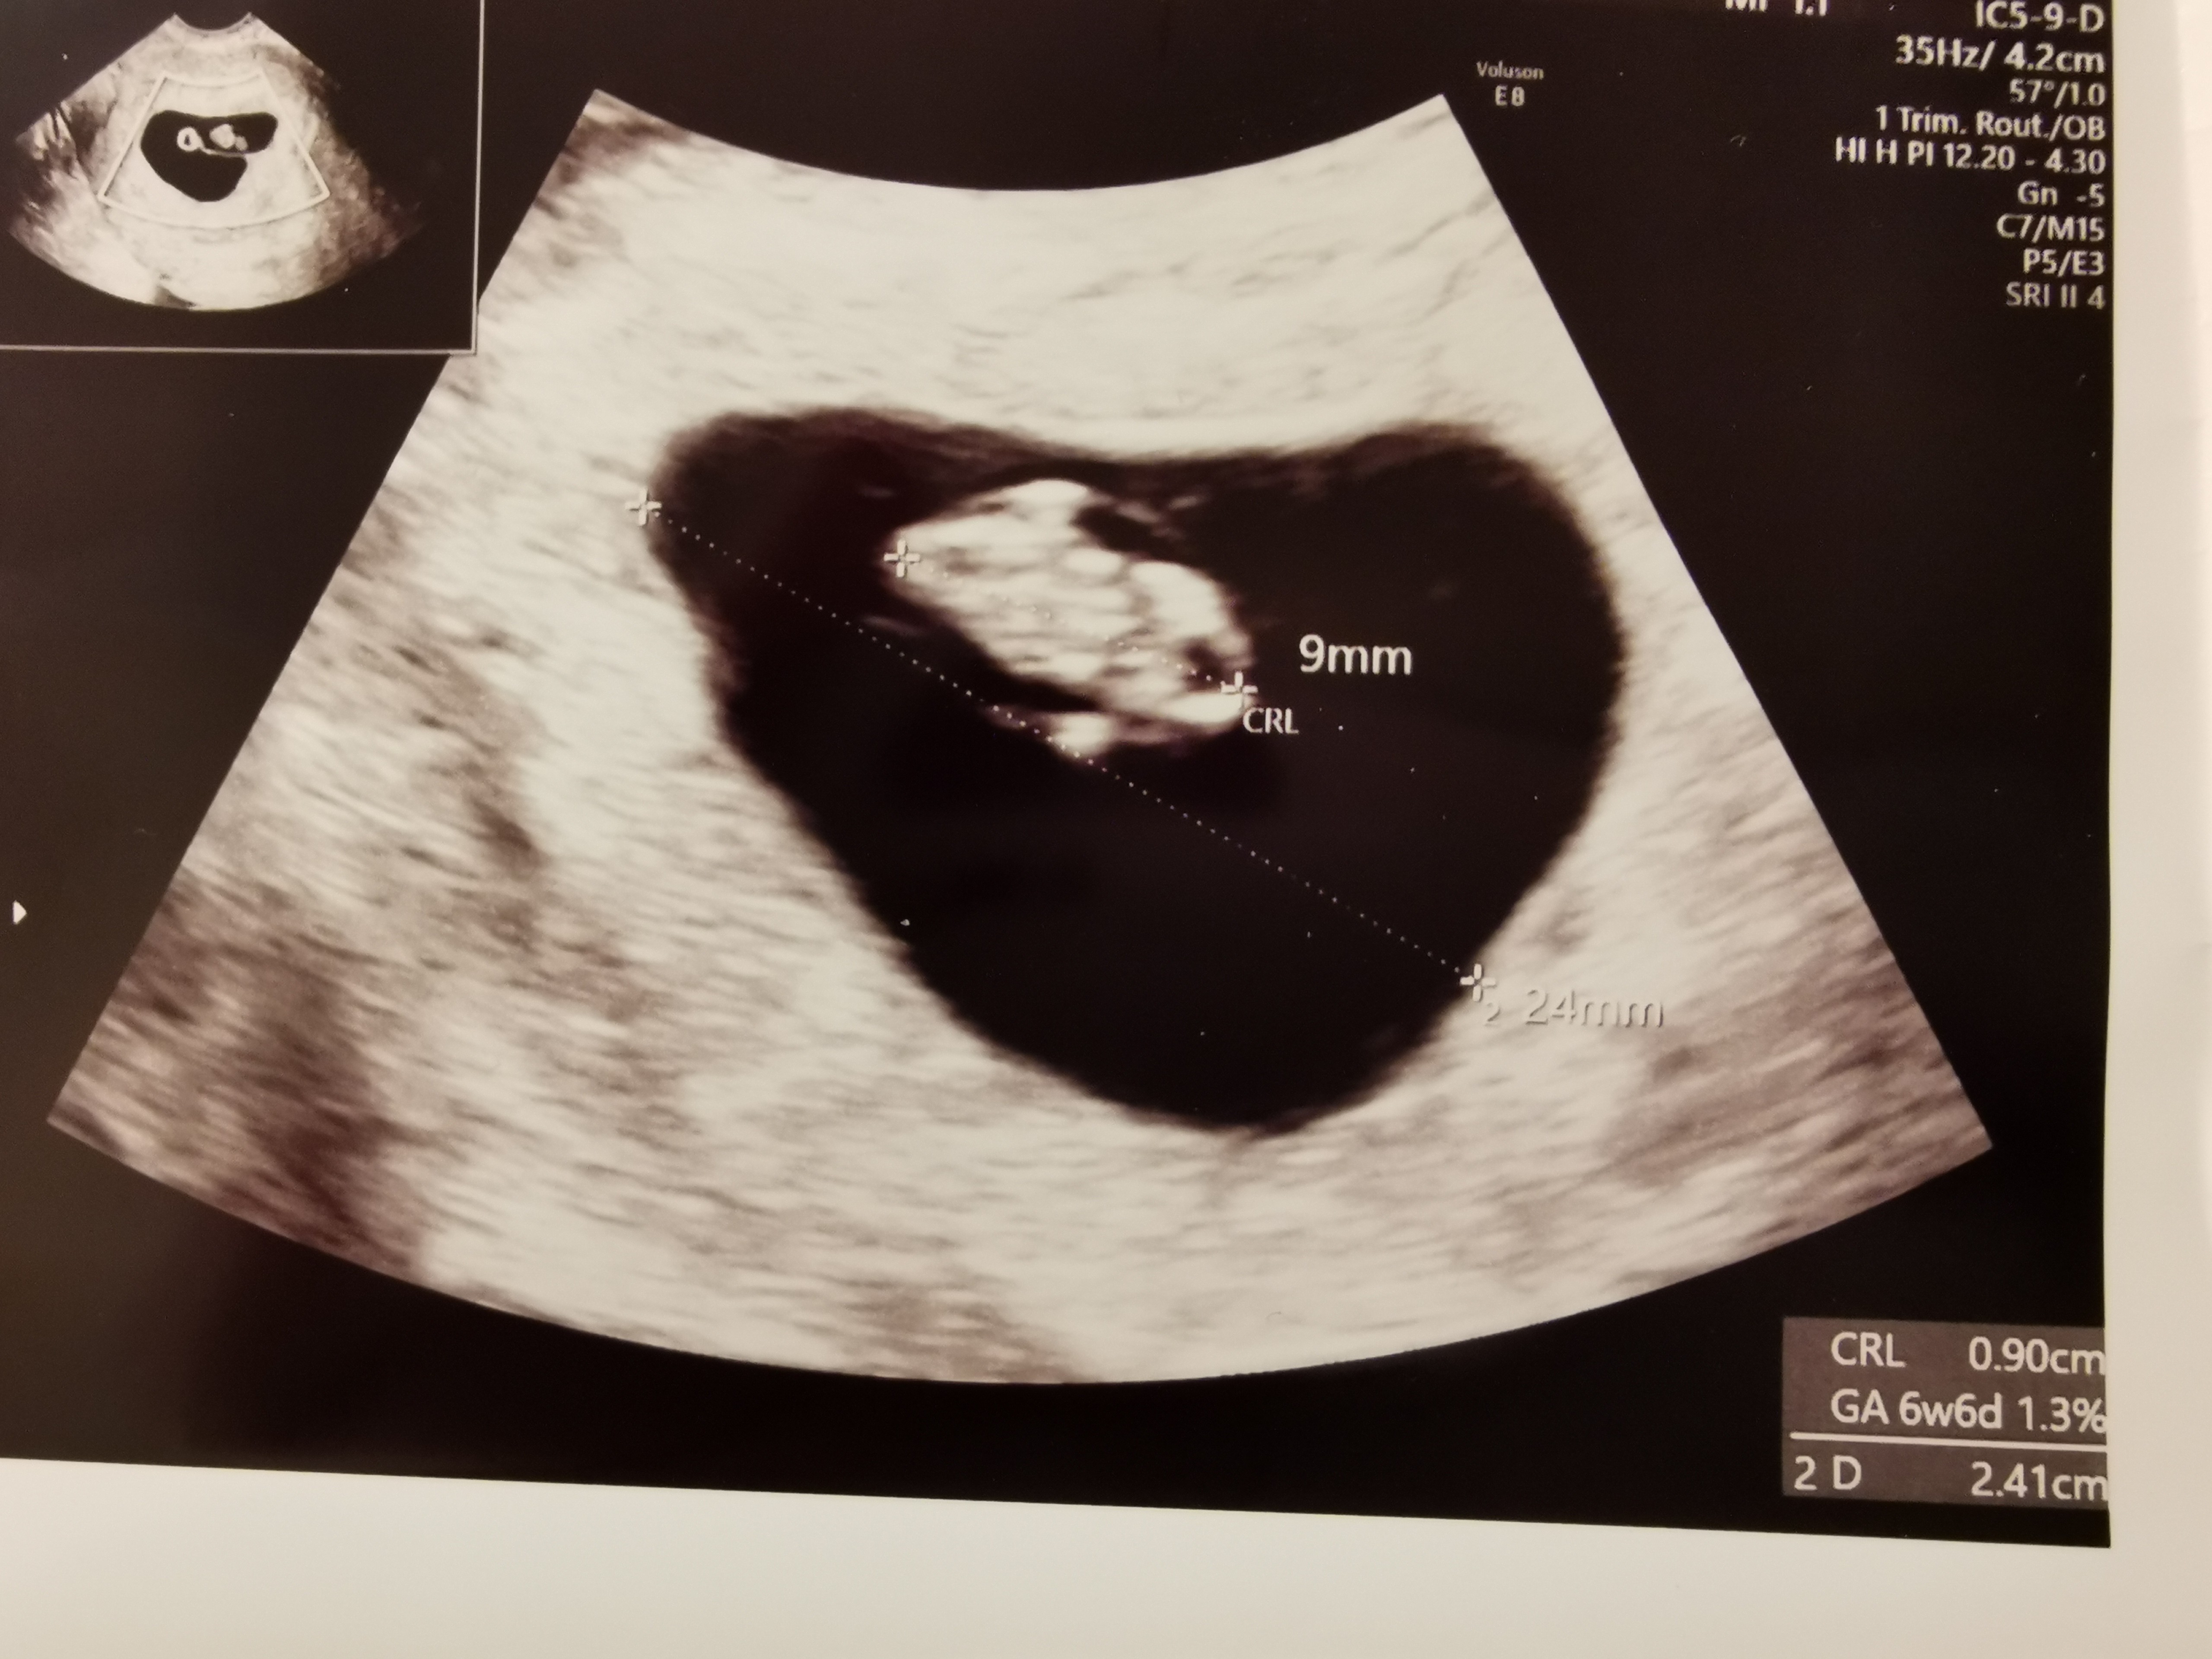

Jestem po wizycie, nie miałam jak napisać wcześniej. Serduszko na całe szczęście jest i bije 140/min. Zarodek 9mm, pęcherzyk 2,4cm. Wg usg 6+6 czyli jest tak jak myślałam.. Ja sama obliczyłam ciąże na 7+0 czyli mało co się pomyliłam. Termin porodu 10 listopada. Z jednej strony jestem szczęśliwa że wszystko dobrze z zarodkiem a z drugiej strony lekarz nie założył mi karty ciąży i kazał zapisać się do poradni ginekologicznej na NFZ.... I powiedział że tam mi założą kartę ciazy, zrobią badania i dadzą zwolnienie.... Jutro muszę iść do roboty bo lekarz zwyczajnie mnie olał.... Chcialam ciąże prowadzić u niego prywatnie ale po dzisiejszym już chyba nie chce... Gdzie ja teraz znajdę lekarza na NFZ na cito żeby zalozyl kartę i dał zwolnienie... Załamka Zobacz załącznik 1095817